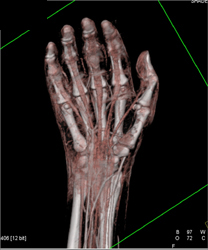

Diagnosis

Sacral and Acetabular Fractures